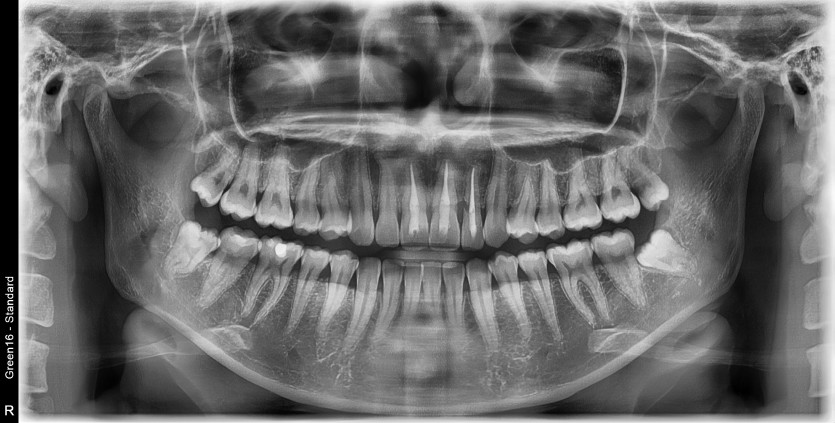

#28,38 사랑니 발치

구강 외과 전문의가 당일 발치했습니다.